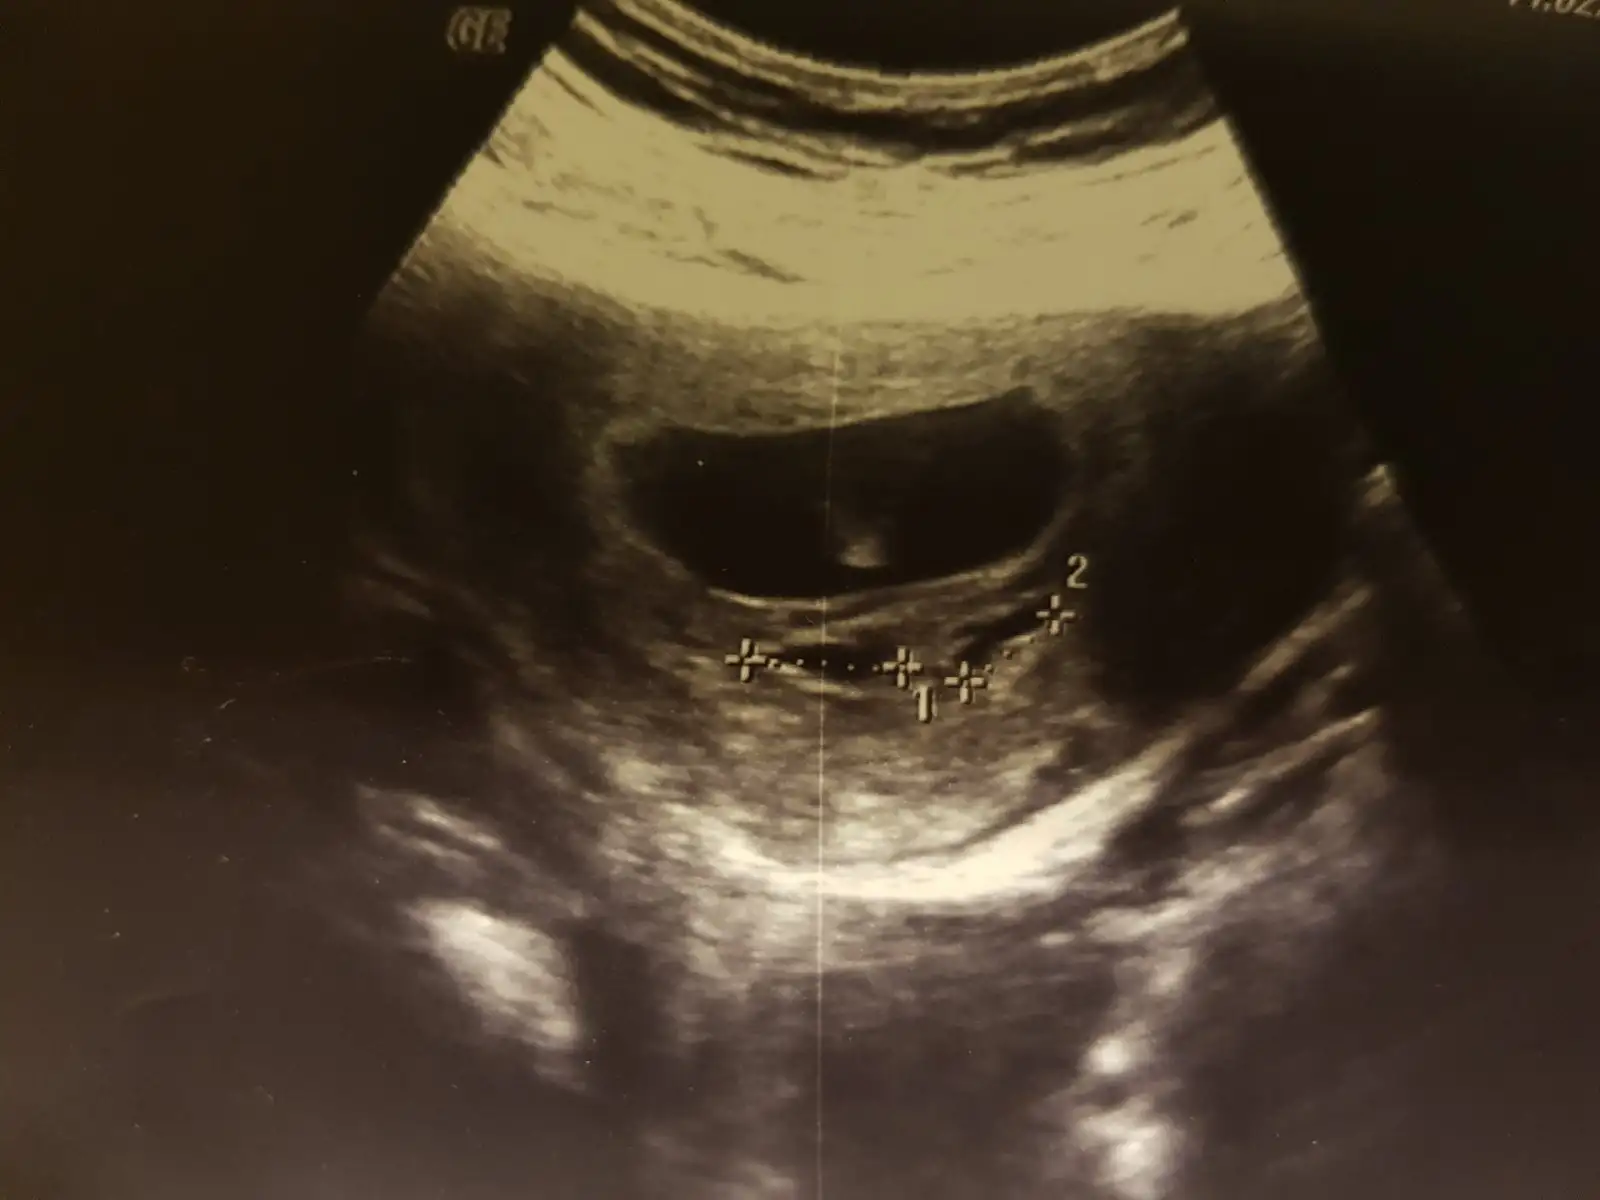

Canim bana da bir yorum yaparsan mutlu olurum sorum biraz zor sanki sag mı sol mu nerde belirsiz benim bebe

Eklentiler

• 15500868715389212413623716523046.webp

31,3 KB · Görüntüleme: 54